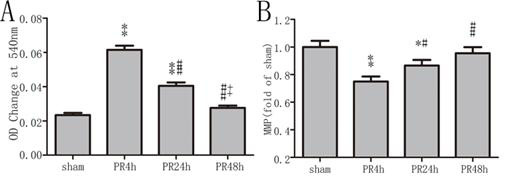

加入氯化钙诱发线粒体肿胀后,各组线粒体在540 nm处吸光度均有下降,PR 4 h及PR 24 h组吸光度下降值均高于sham组(均P < 0.01,图 3),PR 24 h组较PR 4 h组下降程度减轻(P < 0.01),PR 48 h组与sham组比较差异无统计学意义(P > 0.05);PR 4 h及PR 24 h组大鼠心肌MMP较sham组均显著下降(均P < 0.05),PR 24 h组高于PR 4 h组(P < 0.05),PR 48 h组与sham组比较差异无统计学意义(P > 0.05)。

| A:MPTP开放程度的比较;B:MMP的比较;与sham组比较,aP < 0.05和bP < 0.01;与PR 4 h组比较,cP < 0.05和dP < 0.01;与PR 24 h组比较,eP < 0.05 图 3 各组大鼠间MPTP开放程度及MMP的比较 Figure 3 Comparison of MPTP and MMP in each group |

越来越多的研究证实MPTP在发生心功能障碍和细胞死亡的过程中发挥重要作用,MPTP开放状态决定细胞的生死存亡[13]。在可逆性损伤的情况下,MPTP一过性开放,活性氧簇(reactive oxygen species, ROS)过量产生、钙超载引起心肌代谢及功能障碍[14]。若损伤加重,MPTP持续性开放,MMP崩塌、线粒体肿胀破裂,最终引起细胞凋亡或坏死[15]。本研究中,ROSC 4 h时MPTP明显开放、MMP下降,但在48 h时已恢复至正常水平。ROSC 4 h及24 h电镜下见心肌线粒体肿胀、脊稀疏,但结构完整。MPTP一过性开放及心肌超微结构完整也说明心肌的损伤为可逆性。